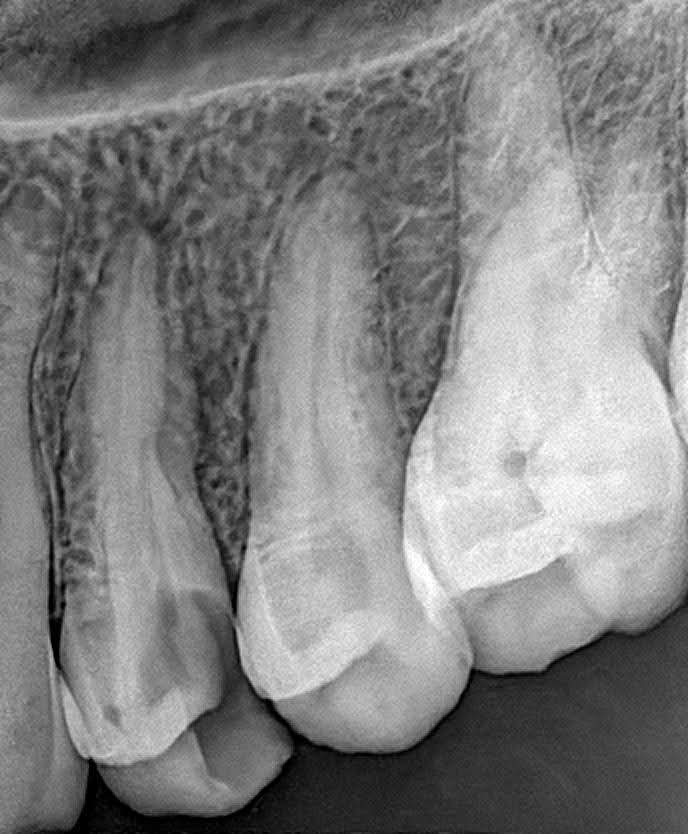

La endodoncia, comúnmente conocida como tratamiento de conducto, es un procedimiento dental que elimina el tejido pulpar afectado. Este tratamiento no solo alivia el dolor, sino que también previene la pérdida de la pieza dental, permitiendo que los pacientes mantengan su sonrisa natural.

Caso clínico realización de Tratamiento de Conducto: